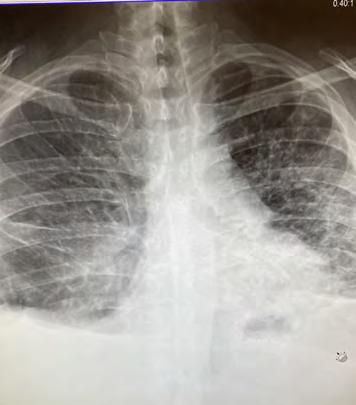

Many calls, however, result in lives being saved, and Marcos has personally been able to keep people alive using his naloxone overdose treatment kit. In October of 2019, he responded to an overdose call for an adult male and used the naloxone kit to keep him alive while waiting for paramedics. Marcos was given a lifesaving award for his actions, as it is believed the man would not have survived otherwise.

Again in February of this year, Marcos expertly administered the overdose treatment, this time to a 2-year-old who had eaten some of his parent’s medication.

“When I arrived to the call, the toddler was coming in and out of consciousness. Based on my training and experience, I knew Percocet to be an opioid derivative and knew that the naloxone treatment could stop or reverse the effects. Also based on the child’s deteriorating condition and knowing the snow was slowing the response time for LifeNet, I administered one dose in the right nostril. A few moments later the child came to, cranky, but otherwise normal.”

Officer Luna received T.A.P.D.’s Lifesaving Award for his efforts on October 15, 2019, while responding to a call. Upon arrival to a residence in College Hill, he observed a white male on the ground. Based on Officer Luna’s training and experience, he knew that the man was overdosing. He administered two doses of naloxone, which more than likely, saved the man’s life.

In 2018, Texarkana Arkansas Police Lieutenant Scott Megason attended training at the Criminal Justice Institute (CJI) in Little Rock to learn how to educate other officers in the use of naloxone kits. Naloxone is a drug that enters the bloodstream and blocks the opiate receptors when people have overdosed.

Arkansas ranks #2 in the nation for opioid overdoses (second to Alabama), but police and doctors are working together to educate and save lives. The CJI kit program started in Benton, Arkansas, in 2016, and since that time, 876 people have been brought back post-overdose after a first responder used a naloxone kit in Arkansas.

Locally, Lt. Megason secured a grant in 2018 through the Blue and You Foundation sponsored by Blue Cross/Blue Shield that provided 100 kits with two doses of naloxone in each kit (at a cost between $120-$140 each). Last year, the Texarkana Arkansas Police Department acquired almost 70 more kits for officers. Since arming local officers with naloxone kits, approximately a dozen people have survived overdoses because of trained and ready officers using naloxone.

Lt. Megason said that the use of naloxone would not be possible locally without the assistance of medical professionals’ assistance, and Dr. Matt Young, in particular. “Dr. Young is the doctor who signs off on our police officers using these kits; he is very active in keeping us educated and current,” said Megason. Dr. Young has worked extensively with area first responders as LifeNet’s Medical Director, so police, fire, medics, EMTs, and volunteers all get direction from Dr. Young and look to his guidance for medical crises. As the medical advisor to the Texarkana Arkansas Police Department, Dr. Young has also established the training protocols for the medicine itself and the use of naloxone kits for emergencies in the field. Dr. Young said, “It is my honor and privilege to serve with the men and women on the front lines to be able to save lives with these kits.” Dr. Young is also a local physician and owner of Texarkana Emergency Center and Hospital.